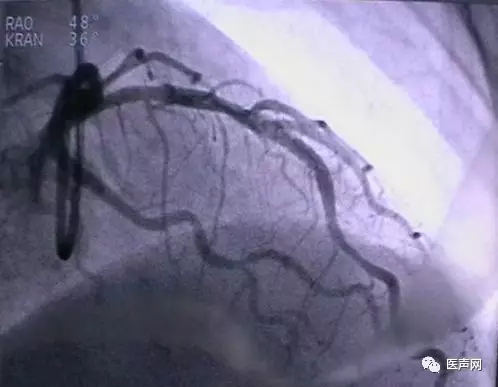

病例3:LAD中段90%狭窄

操作过程:JL4导引导管同轴性不好,支撑力不够,直接支架术(direct stent)有阻力,改用EBU 导引导管---植入TAXCOR 3.0×18mm DES.说明:导引导管的重要性。下图所示: